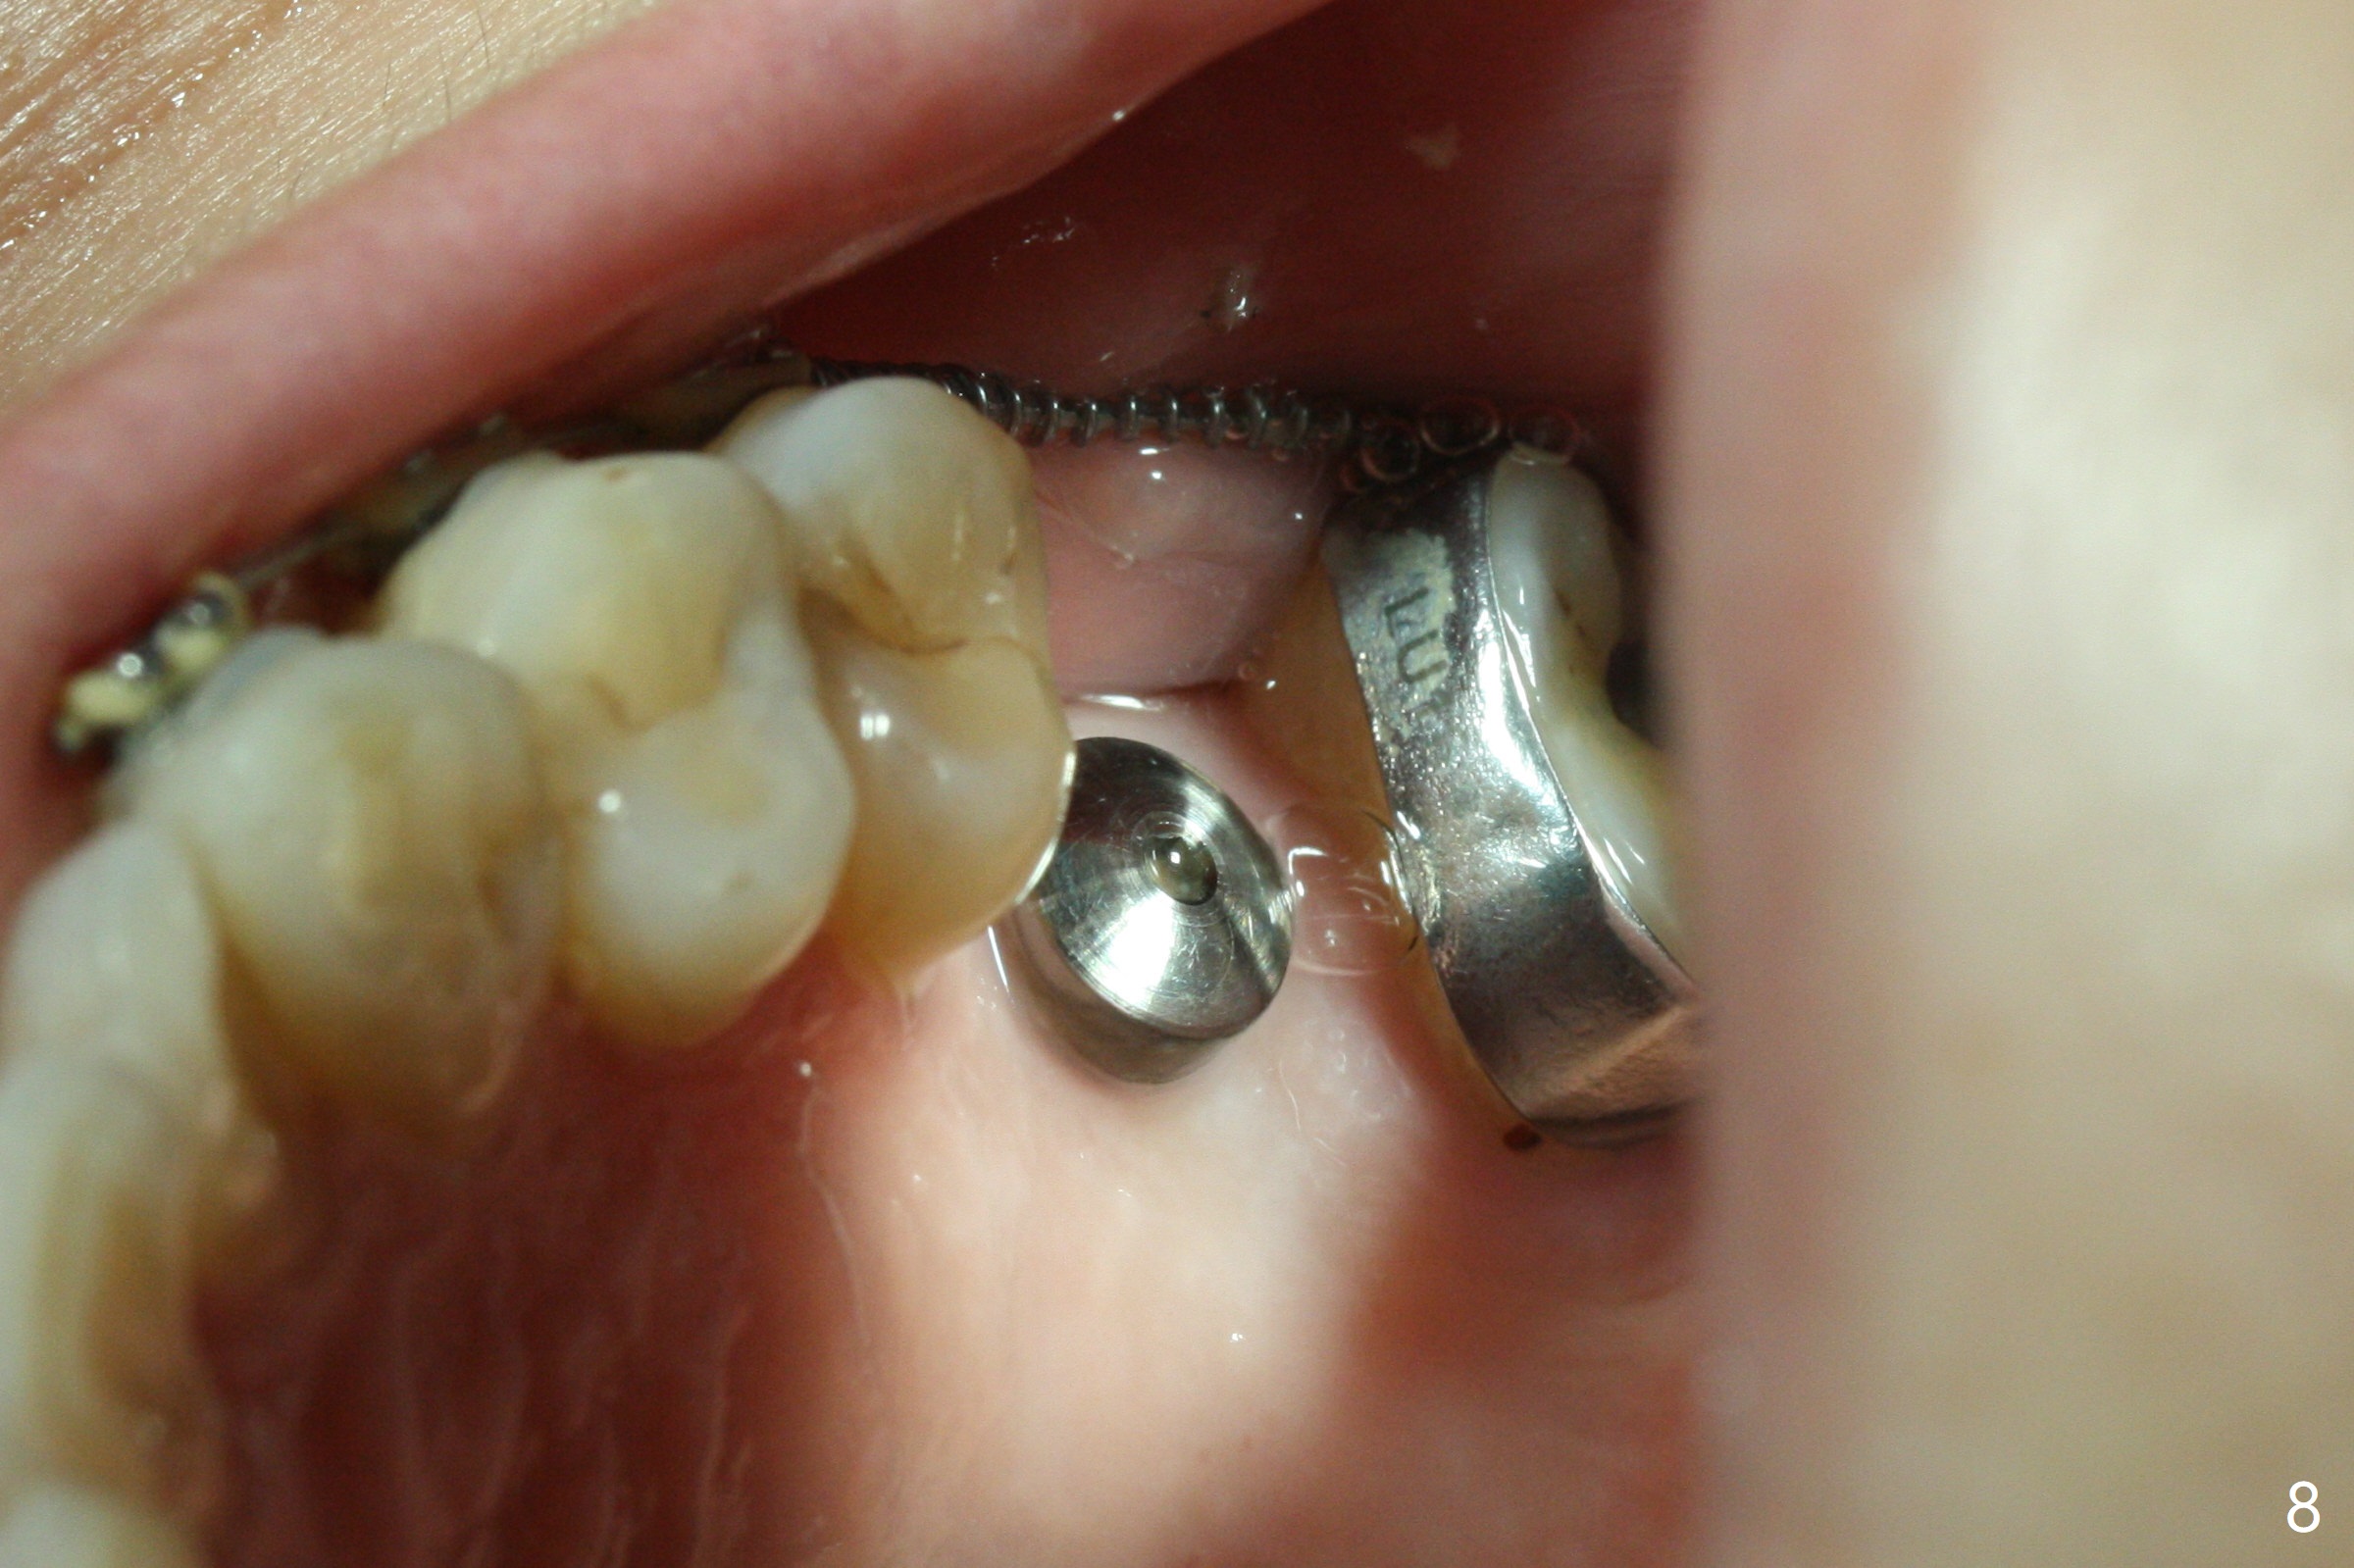

Seven months of orthodontic treatment and 2 months post implant placement, the edentulous mesiodistal space appears to return normal, but the implant has pain when the healing abutment is retightened (Fig.8). Since the patient is going to return home country for reunion, the last two anterior brackets at #6 and 7 are remove and the arch wire is shortened for cosmetics (Fig.9).